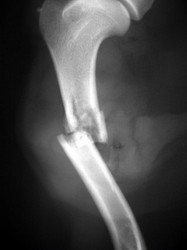

PRÁCTICAS CURSO DE FIJACIÓN EXTERNA PERFECCIONAMIENTO.

Húmero.